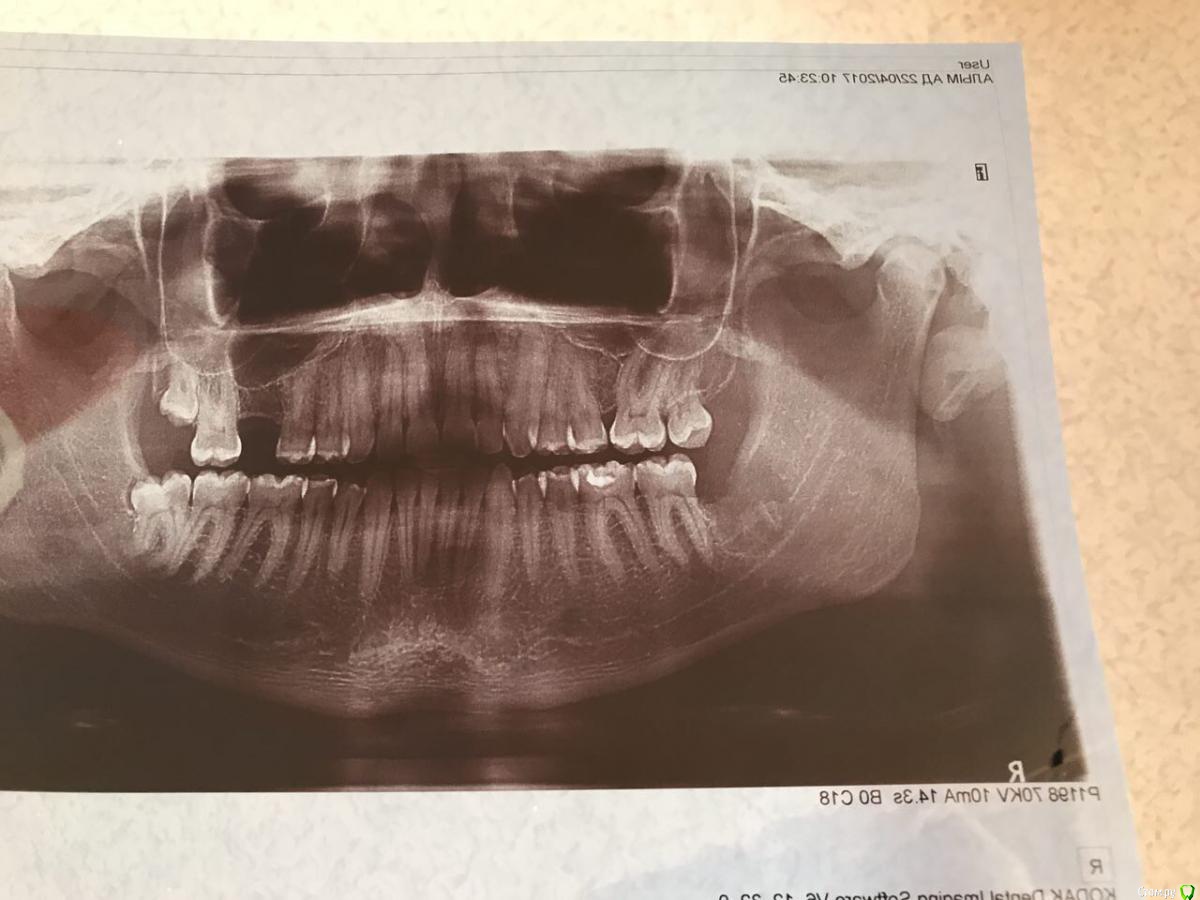

На днях пришёл с этой проблемой, сделали снимок панорамный(приложу). Врач сказал ни его не осталось и это хорошо.

Подскажите куда и к кому идти, и точно ли на снимке все хорошо, мне кажется, что там кусочек корня остался.

post-51569-0-90322000-1494852415_thumb.jpg